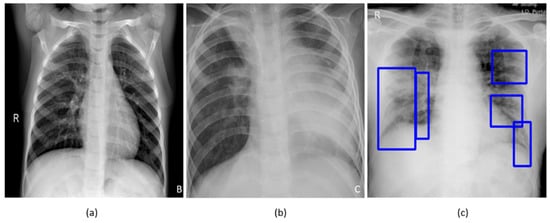

A study of the literature shows that individuals suffering from COVID-19 disease commonly present with hyperthermia and difficulty with breathing. The disease manifests in the lungs as ground-glass opacities, with peripheral, bilateral, and predominant basal distribution [2]. These patterns are visually similar to, yet distinct from, those caused by non-COVID-19-related viral pneumonia and those caused by other bacterial and fungal pathogens [2]. Further, the current literature studies revealed that it is difficult to distinguish viral pneumonia from others caused by bacterial and fungal pathogens [4]. Figure 1 shows instances of chest X-rays (CXRs) of clear lungs, bacterial pneumonia, and COVID-19-related pneumonia, respectively.

Figure 1. Chest X-rays (CXRs) showing (a) clear lungs; (b) bacterial pneumonia infection manifesting as consolidations in the right upper lobe and retro-cardiac left lower lobe; and (c) COVID-19 pneumonia infection showing bilateral manifestations. Blue frames in (c) denote radiologist annotations indicating disease regions, which serve as ground truth in our analysis.